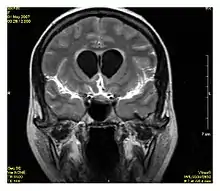

| Fluid-attenuated inversion recovery | FLAIR | Fluid suppression by setting an inversion time that nulls fluids | High signal in lacunar infarction, multiple sclerosis (MS) plaques, subarachnoid haemorrhage and meningitis (pictured).[15] | ![]() | |

Inversion recovery

Inversion recovery is an MRI sequence that provides high contrast between tissue and lesion. It can be used to provide high T1 weighted image, high T2 weighted image, and to suppress the signals from fat, blood, or cerebrospinal fluid (CSF).[40]